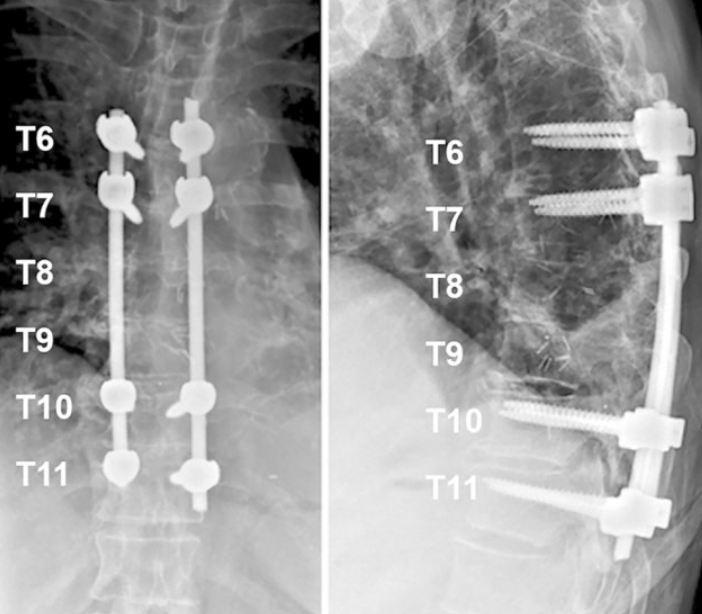

Stabilization

Rods or screws are added for stability when needed.